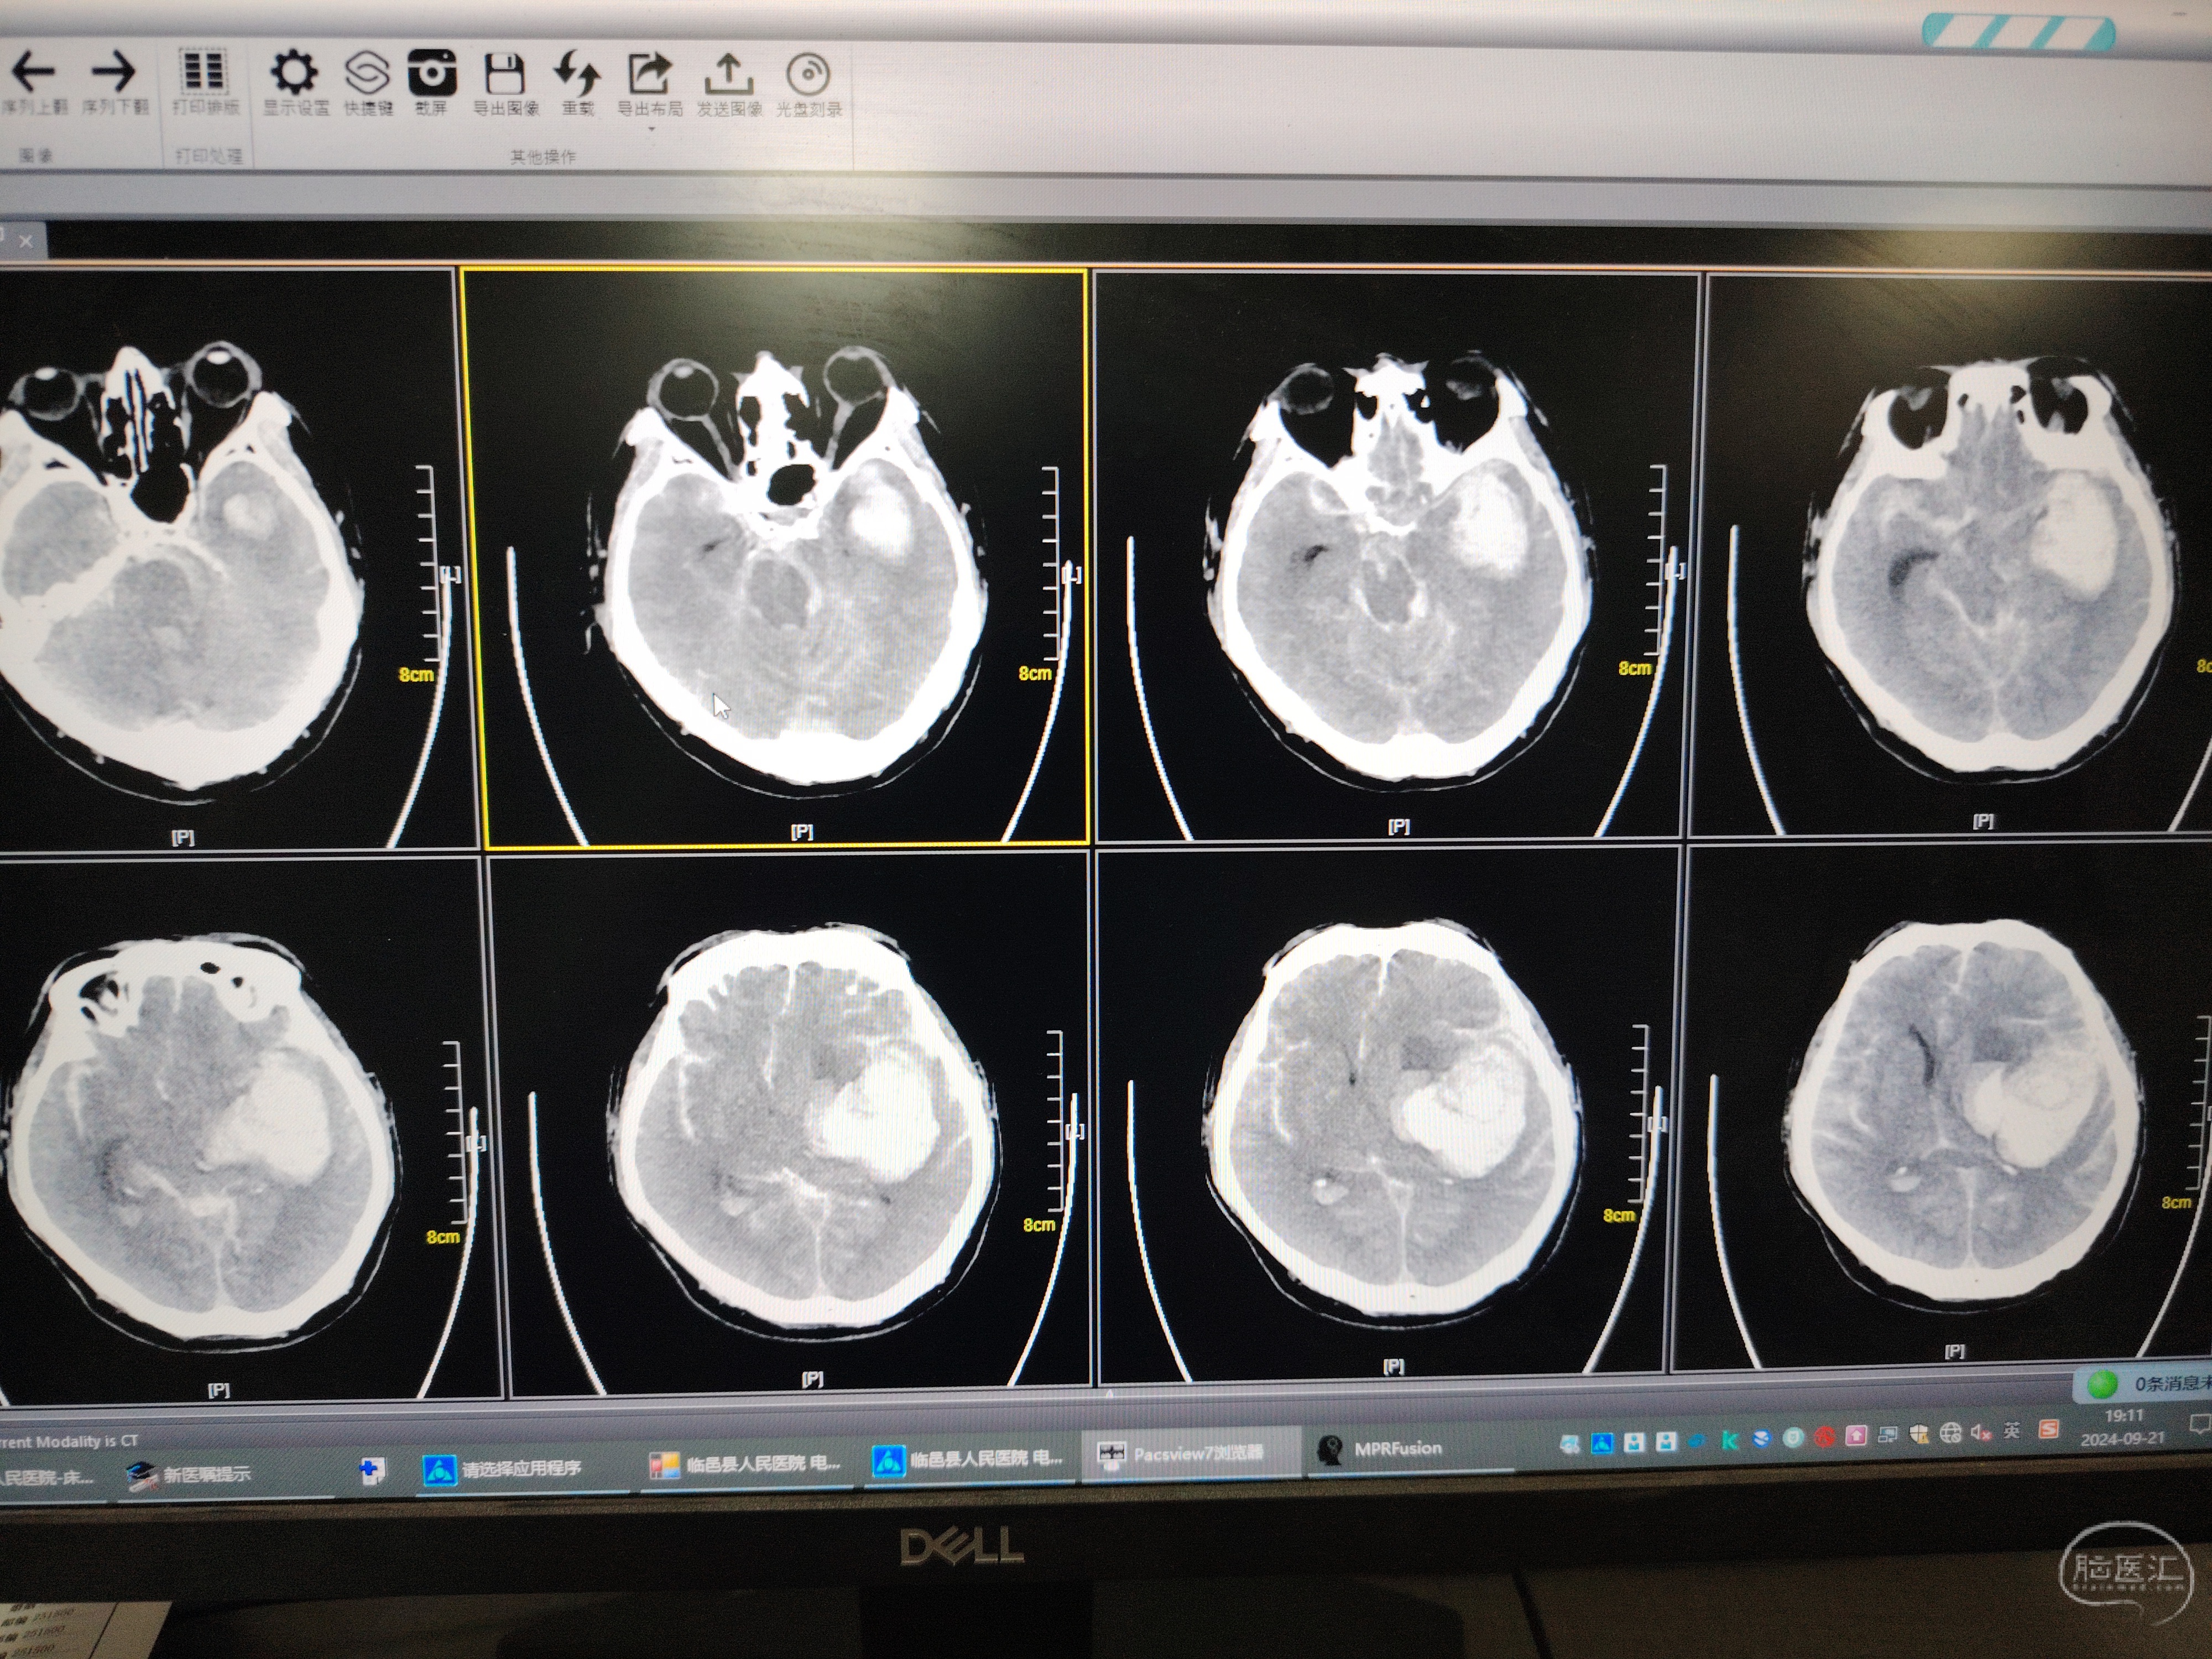

2.查体:深昏迷,气管插管状态,查体不合作。两侧曈孔等大等圆,直径约6mm,对光反射消失。颈无抵抗,无强直头位。双肺呼吸音粗糙,双肺未闻及干湿性啰音。四肢肌力检查不配合,肌张力增高。入院ct左颞叶高密度影,边缘清晰,CT值约70HU,周围见水肿带围绕,蛛网膜下腔及脑室内可见高密度铸型, 左侧脑室、环池受压,中线结构向右侧移位。【印象】左侧颞叶、基底节区出血,血肿破入蛛网膜下腔及脑室;伴脑疝形成。